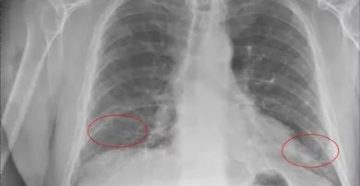

Уплотнение междолевой плевры справа что это || Уплотнение междолевой плевры справа что это Плеврит –…